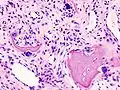

Histopathology of osteoarthrosis of a knee joint in an elderly female -